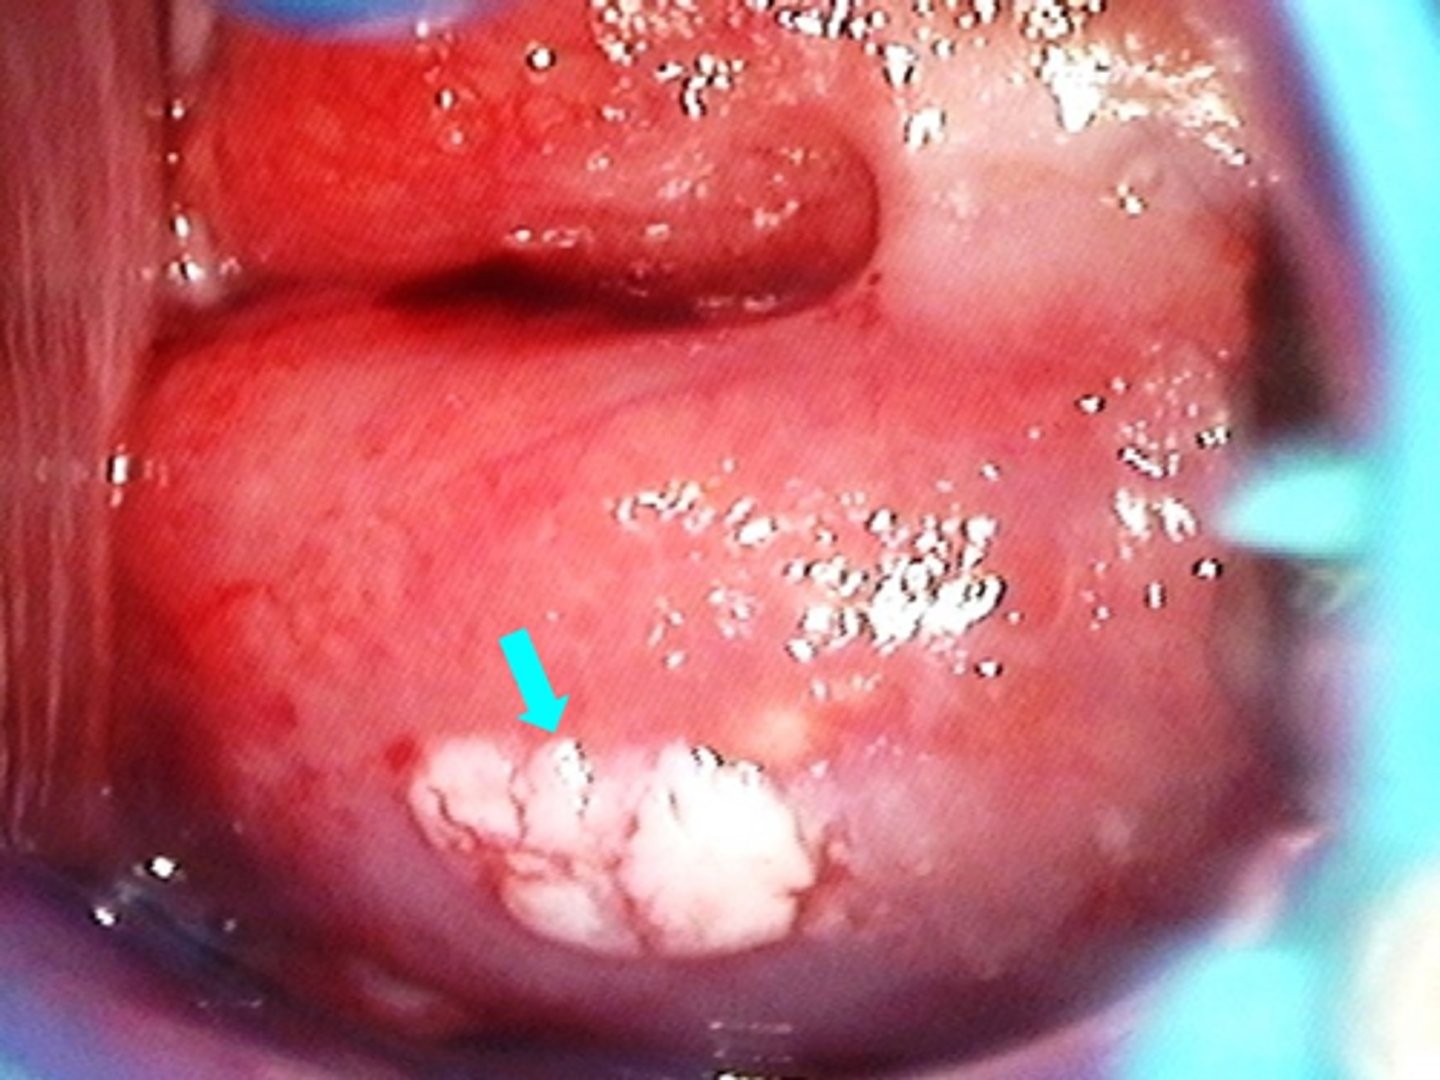

condyloma acuminatum

Papillary growths affecting the perineum, anus, vulva, vagina, cervix, and oropharynx

Caused by “low risk” strains of single stranded DNA virus, human papilloma virus (HPV)

what strains of HPV typically cause condyloma acuminatum?

how does condyloma acuminatum present?

Whitish or flesh-colored papillomatous growths with “cauliflower” appearance ranging from small single lesions to large coalescing growths